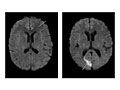

Abnormal:

Tumours in the brain or in areas outside the brain, such as an acoustic neuroma, are present.

Bleeding or swelling (edema) in or around the brain is present.

Areas of infection or inflammatory disease, such as encephalitis or meningitis, are present.

Abnormal areas in the brain may mean that certain diseases, such as Huntington's disease, multiple sclerosis, Parkinson's disease, or Alzheimer's disease, are present.

Bulges or weak areas (aneurysms) or abnormal blood vessels (such as an AV malformation) are present.